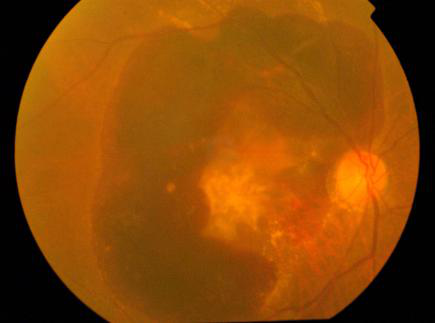

黄斑位于视网膜的中心位置,该区域拥有丰富的感光细胞,也是眼睛感光的重要部位。当黄斑区域发生了视网膜缺损病变,就称为黄斑裂孔。

根据病变的位置、大小以及病程进展,黄斑裂孔分为4期:

1期、板层裂孔:此时裂孔并未完全穿透视网膜神经层。中央凹部分发生脱离为1a期;黄斑中央凹进一步脱离,中央凹陷消失为1b期。

2期、全层裂孔:裂孔直径﹤400微米。

3期、全层裂孔:裂孔直径≥400微米,未发生玻璃体后脱离。

4期、全层裂孔:裂孔直径≥400微米,发生玻璃体后脱离。

在黄斑裂孔的早期(1-2期),视网膜仅发生撕裂但并未出现严重的神经损伤,若这时能及时进行手术治疗,可以使得裂孔闭合并改善视力。当病变恶化至3、4期,患者的视力可能已经发生严重受损,即使通过手术封闭裂孔,已经损伤的视神经也很难修复。

珠海希玛林顺潮眼科医院通过光学相干断层扫描对黄斑裂孔进行诊断,可以准确量度裂孔的大小以及位置等,帮助患者及早诊断黄斑裂孔及其严重程度,从而制定合理的治疗方案。